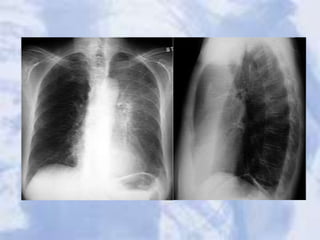

Lung Anatomy on Chest X-ray

• PA View:

– Extensive overlap

– Lower lobes extend

high

• Lateral View:

– Extent of lower lobes